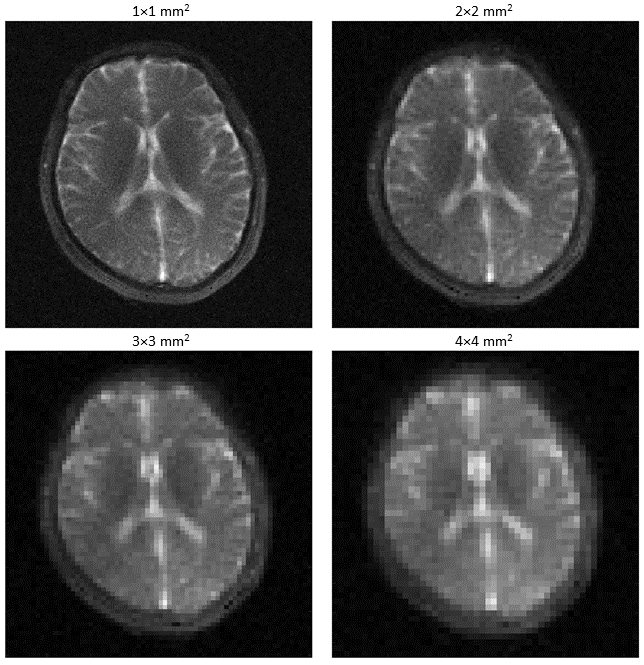

Refer to caption

Figure 9: In vivo sodium MRI scans performed with a 15 ms readout duration at four different resolutions.

3.3 In vivo experiment

Figure 9 shows the in vivo results. The scan with the highest resolution yielded a sharp brain image with a great amount of detail. Although no clear border between WM and GM could be observed, the CSF in the ventricles and outer parts of the brain was well defined. As expected, with the reduction of resolution (increased pixel size), the images became much blurrier, and the border between WM/GM and CSF faded away at lower resolutions. The decay in all tissues and fluids lead to strong blurring. In particular, the intensified CSF blurring resulted in increased brightness in WM and GM.